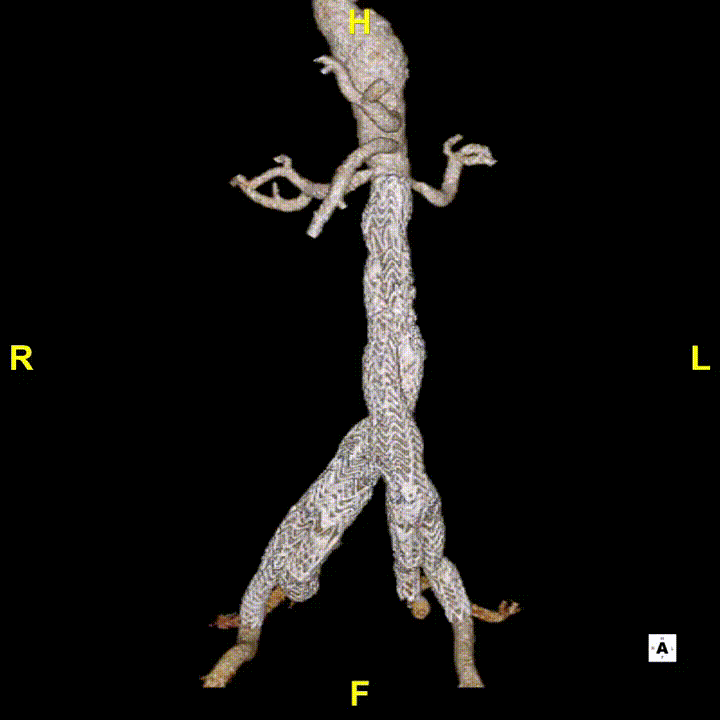

② 八爪鱼支架(多分支支架)的应用

用于内脏区全腔内重建,该技术顺应血流方向,不改变血流动力学,中期疗效确切。

特殊处理:腹腔干可栓塞。

注意:避免倒置操作,减少血栓形成风险。